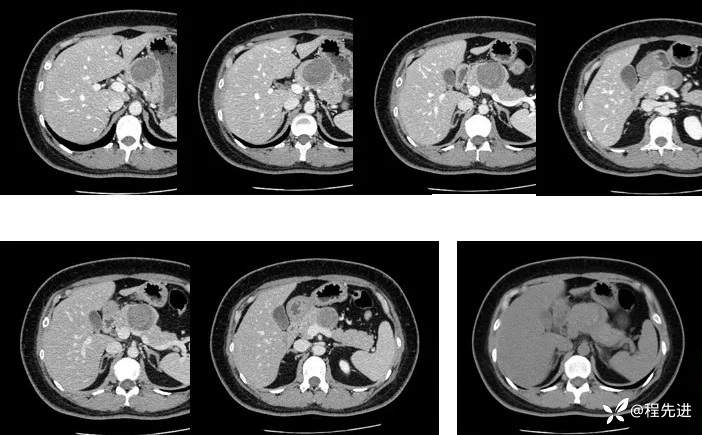

CT平扫+增强

上排动脉期,下排静脉期、平扫